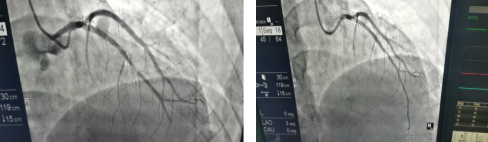

相关影像:

术前(前降支中段狭窄严重,远段血流差) 术后(前降支狭窄消失,远段血流恢复)